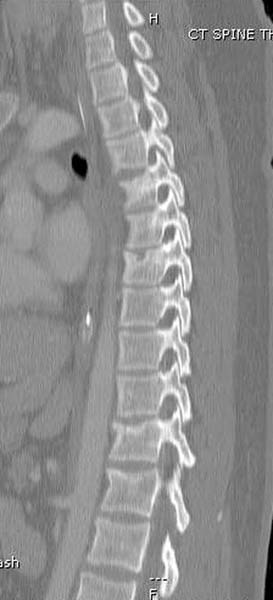

Вообщем.., больная поступает около 2.00 дня и дальнейщая хронология: 2.27 PМ рентген грудной клетки; 2.54 РМ рентген бедра; 2.53-3.06 КТ скан, всего около 2000 срезов. Из-за беспокойства пациента (алкоголь), множественные переломы ребер – трубка в превральную полость и интубация. Около 3.45 в операционной эксплуараторная лапароскопия с последующим ушиванием брюшной полости.

Перелом позвоночника и боковую компрессию таза отнесли к стабильным переломам и не стали форсировать события до лучших времен...